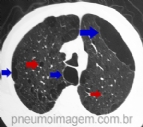

DESTAQUES DO ERS2016: HEMORRAGIA ALVEOLAR DIFUSA (HAD)

A HAD é uma doença rara, mas muito grave. Os achados típicos à TC de tórax são opacidades bilaterais e difusas em vidro fosco, frequentemente dos ápices até os ângulos costofrênicos. A terça parte dos pacientes não tem hemoptise à apresenta...